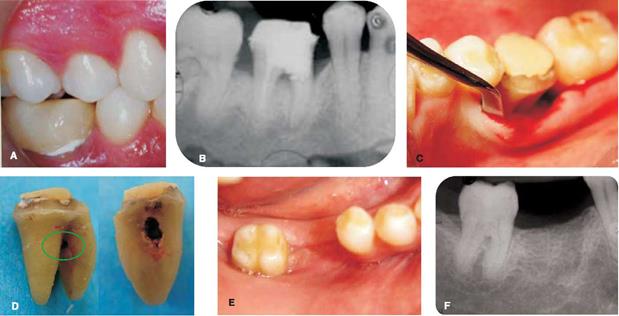

En un segundo procedimiento se realizó cirugía de desbridamiento por colgajo en los dientes 22, 26, 27, 36, 37, colocando membrana de colágena absorbible y xenoinjeto óseo en el diente 26, en los dientes 36 y 37 se colocó xenoinjerto óseo, se prescribió amoxicilina de 500 mg ( Figura 2).

Figura 2 Fotografía preoperatoria clínica y radiográfica (A,B), defecto intraóseo (C) y colocación de xenoinjerto óseo y membrana de colágena en molar 26 (D). Situación clínica (E) y radiográfica (F) 12 meses después de la cirugía.

A la revaloración no se hallaron bolsas periodontales, lo cual indica que los procedimientos quirúrgicos fueron favorables, además, radiográficamente aumentó la altura ósea, en la zona donde se colocó membrana de colágena y xenoinjerto óseo.

En los sitios donde se colocó membrana de colágena, los resultados fueron favorables al realizar la revaloración,y a que bolsas de 8 y10mm,disminuyerona 3 mm. Diversos estudios clínicos, han sido publicados, mostrando la efectividad de la membrana de colágena, por ejemplo Becker y cols,15 y Tonetti y cols, reportaron una ganancia de inserción de 3.0 mm y 2.9 mm, respectivamente.13